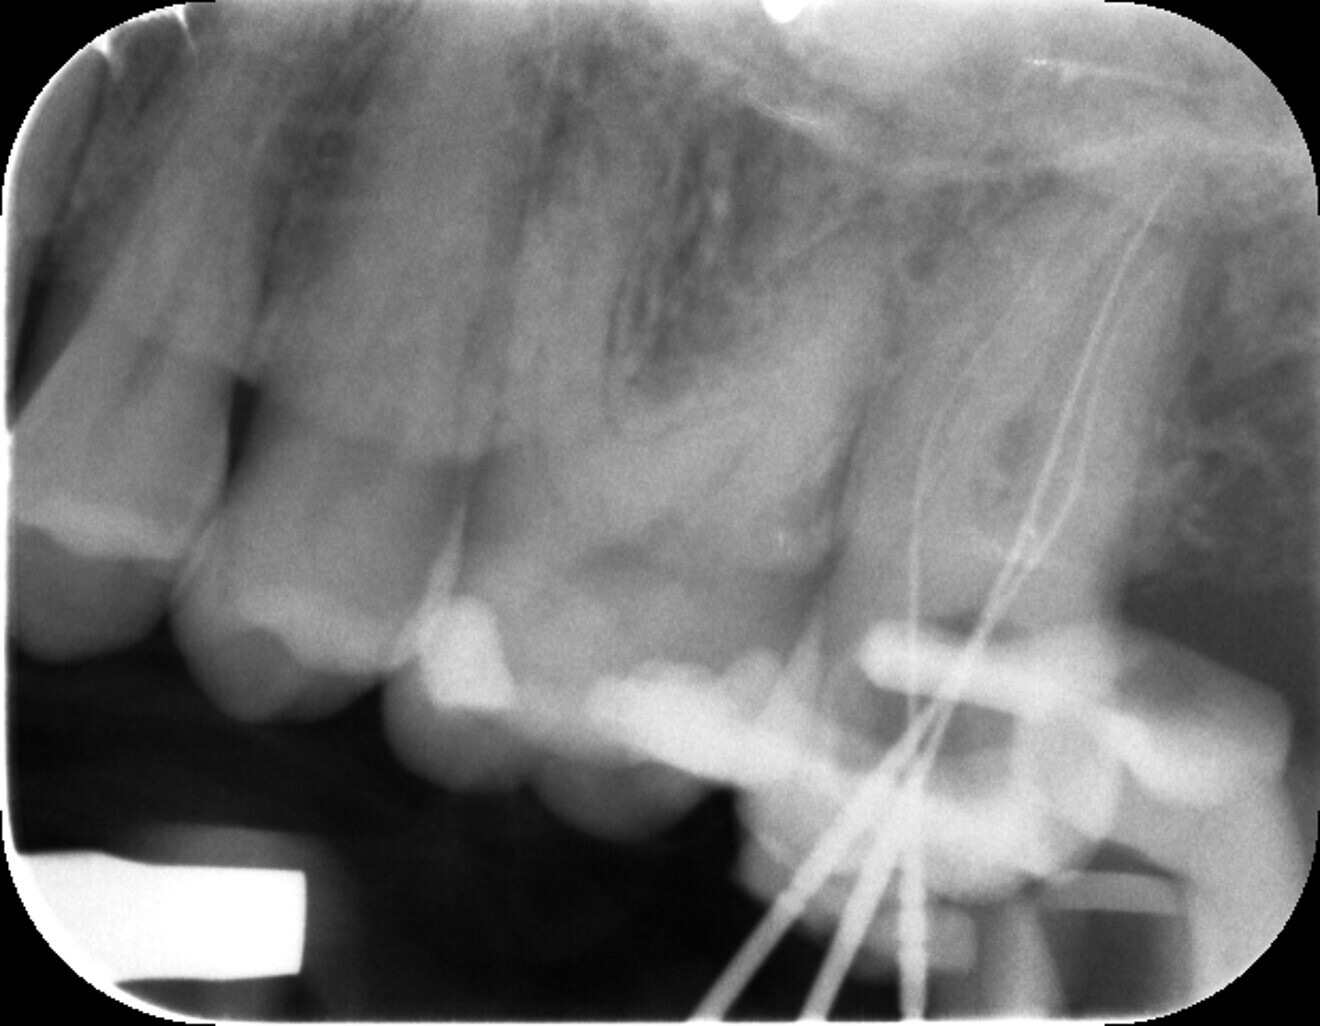

Fig. 1: Pre-op radiograph of tooth #27.

In February 2024, a 46-year-old female patient presented to our practice with severe pain in her left upper jaw. After a positive vitality test and strong response to the percussion test, a diagnosis of irreversible pulpitis of tooth #27 was confirmed radiographically (Fig. 1). The patient agreed to a two-session root canal treatment, which was started at the first appointment.